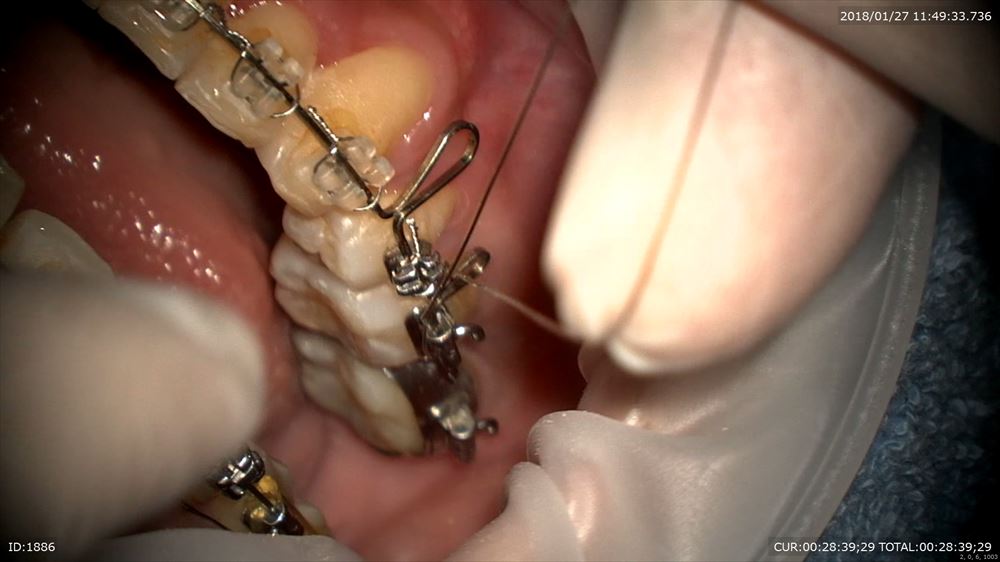

最後は矯正。4番の抜歯スペースのリトラクションの最終段階とトルクコントロール同時

マイクロで観察。トーイン。テイップバック

これでOK。春には外します!口元も綺麗になりました。